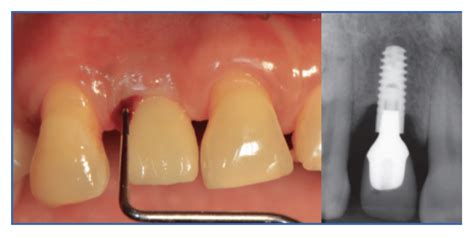

- Evaluación clínica de la encía: Primero, examinamos cuidadosamente la zona alrededor del implante. Observamos si hay enrojecimiento, inflamación o recesión de la encía, y si se produce sangrado al sondear. El sondeo periimplantario se hace con una sonda periodontal milimetrada, deslizando suavemente entre la encía y el implante para medir la profundidad de la bolsa. En un implante sano, la sonda penetra solo 2-3 mm y no hay sangrado. En la periimplantitis podemos encontrar bolsas profundas (por ejemplo >5 mm) y sangrado e incluso pus al sondear. La presencia de supuración (pus) al presionar la encía es prácticamente diagnóstico de infección activa.

- Radiografías dentales: La confirmación de la periimplantitis suele requerir radiografías, típicamente radiografías periapicales o panorámicas de la zona del implante. En la radiografía buscamos evidencias de pérdida ósea alrededor del implante comparado con radiografías tomadas justo después de colocarlo. Un signo típico es un cráter o sombra alrededor de la rosca del implante indicando que el hueso se ha reabsorbido. Si disponemos de radiografías anteriores, podemos determinar cuánto hueso se ha perdido con el tiempo. Incluso una pérdida ósea mínima (por ejemplo 2-3 mm) acompañada de inflamación nos haría diagnosticar periimplantitis incipiente.

Un aspecto del diagnóstico es determinar si el caso es solo mucositis (encía inflamada pero hueso intacto) o ya es periimplantitis (con pérdida ósea). Esto se clarifica combinando el sondeo y la radiografía. Si hay sangrado al sondeo pero la radiografía muestra el hueso intacto, hablaríamos de mucositis periimplantaria. En cambio, si la radiografía muestra periimplante con pérdida ósea (por ejemplo se ven expiras del implante descubiertas) junto con inflamación clínica, entonces es periimplantitis.

El diagnóstico de periimplantitis se basa en examinar las encías del implante, medir las bolsas alrededor y comprobar en radiografías si hay pérdida de hueso.